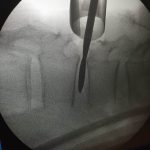

Lumbar intervertebral foramina epidural nerve root injection

After injecting spinal nerve roots with anesthesia, confirming the cause of spinal sciatica symptoms. I can tell the patient whether lumbar screw fusion is helpful.